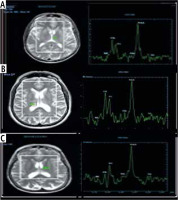

The MRS characteristics in the basal ganglia or thalamus demonstrated an increase in the brain metabolite Glx with a significant correlation to the presence and grade of HE, as we found its presence with low amounts in the control group, whereas in overt HE, we found large amounts of Glx in the brain with a significant difference (p = 0.001). Other brain metabolites, such as Cho and mI, were present in large quantities in the control group, as shown in Figure 1, which displayed a normal MRS evaluation spectrum. However, in the overt HE groups, we observed a significant decline in their quantities (p = 0.001). Two brain metabolites (NAA and Cr) were not significantly different between all grades of HE and the control groups (p = 0.47 and 0.38, respectively) (Table 3, Fig. 2).

Fig. 2

Magnetic resonance spectroscopy (MRS) in: A) a healthy patient, B) a cirrhotic patient with minimal hepatic encephalopathy (MHE), and C) a cirrhotic patient with overt HE showing increase of glutamate/glutamine complex (Glx) in cirrhotic patient with MHE and marked increase of Glx in cirrhotic patients with overt HE, decrease of myoinositol and choline values in cirrhotic patient with MHE and marked decrease in cirrhotic patient with overt HE. The region of interest (ROI) was located in the thalamus on MRS

In cirrhotic patients with MHE and over HE, the ratios of integrals of various metabolites were calculated and revealed that Glx/Cr was significantly increased, whereas mI/Cr and Cho/Cr were significantly decreased. There was no significant difference in NAA/Cr ratio (Table 4).